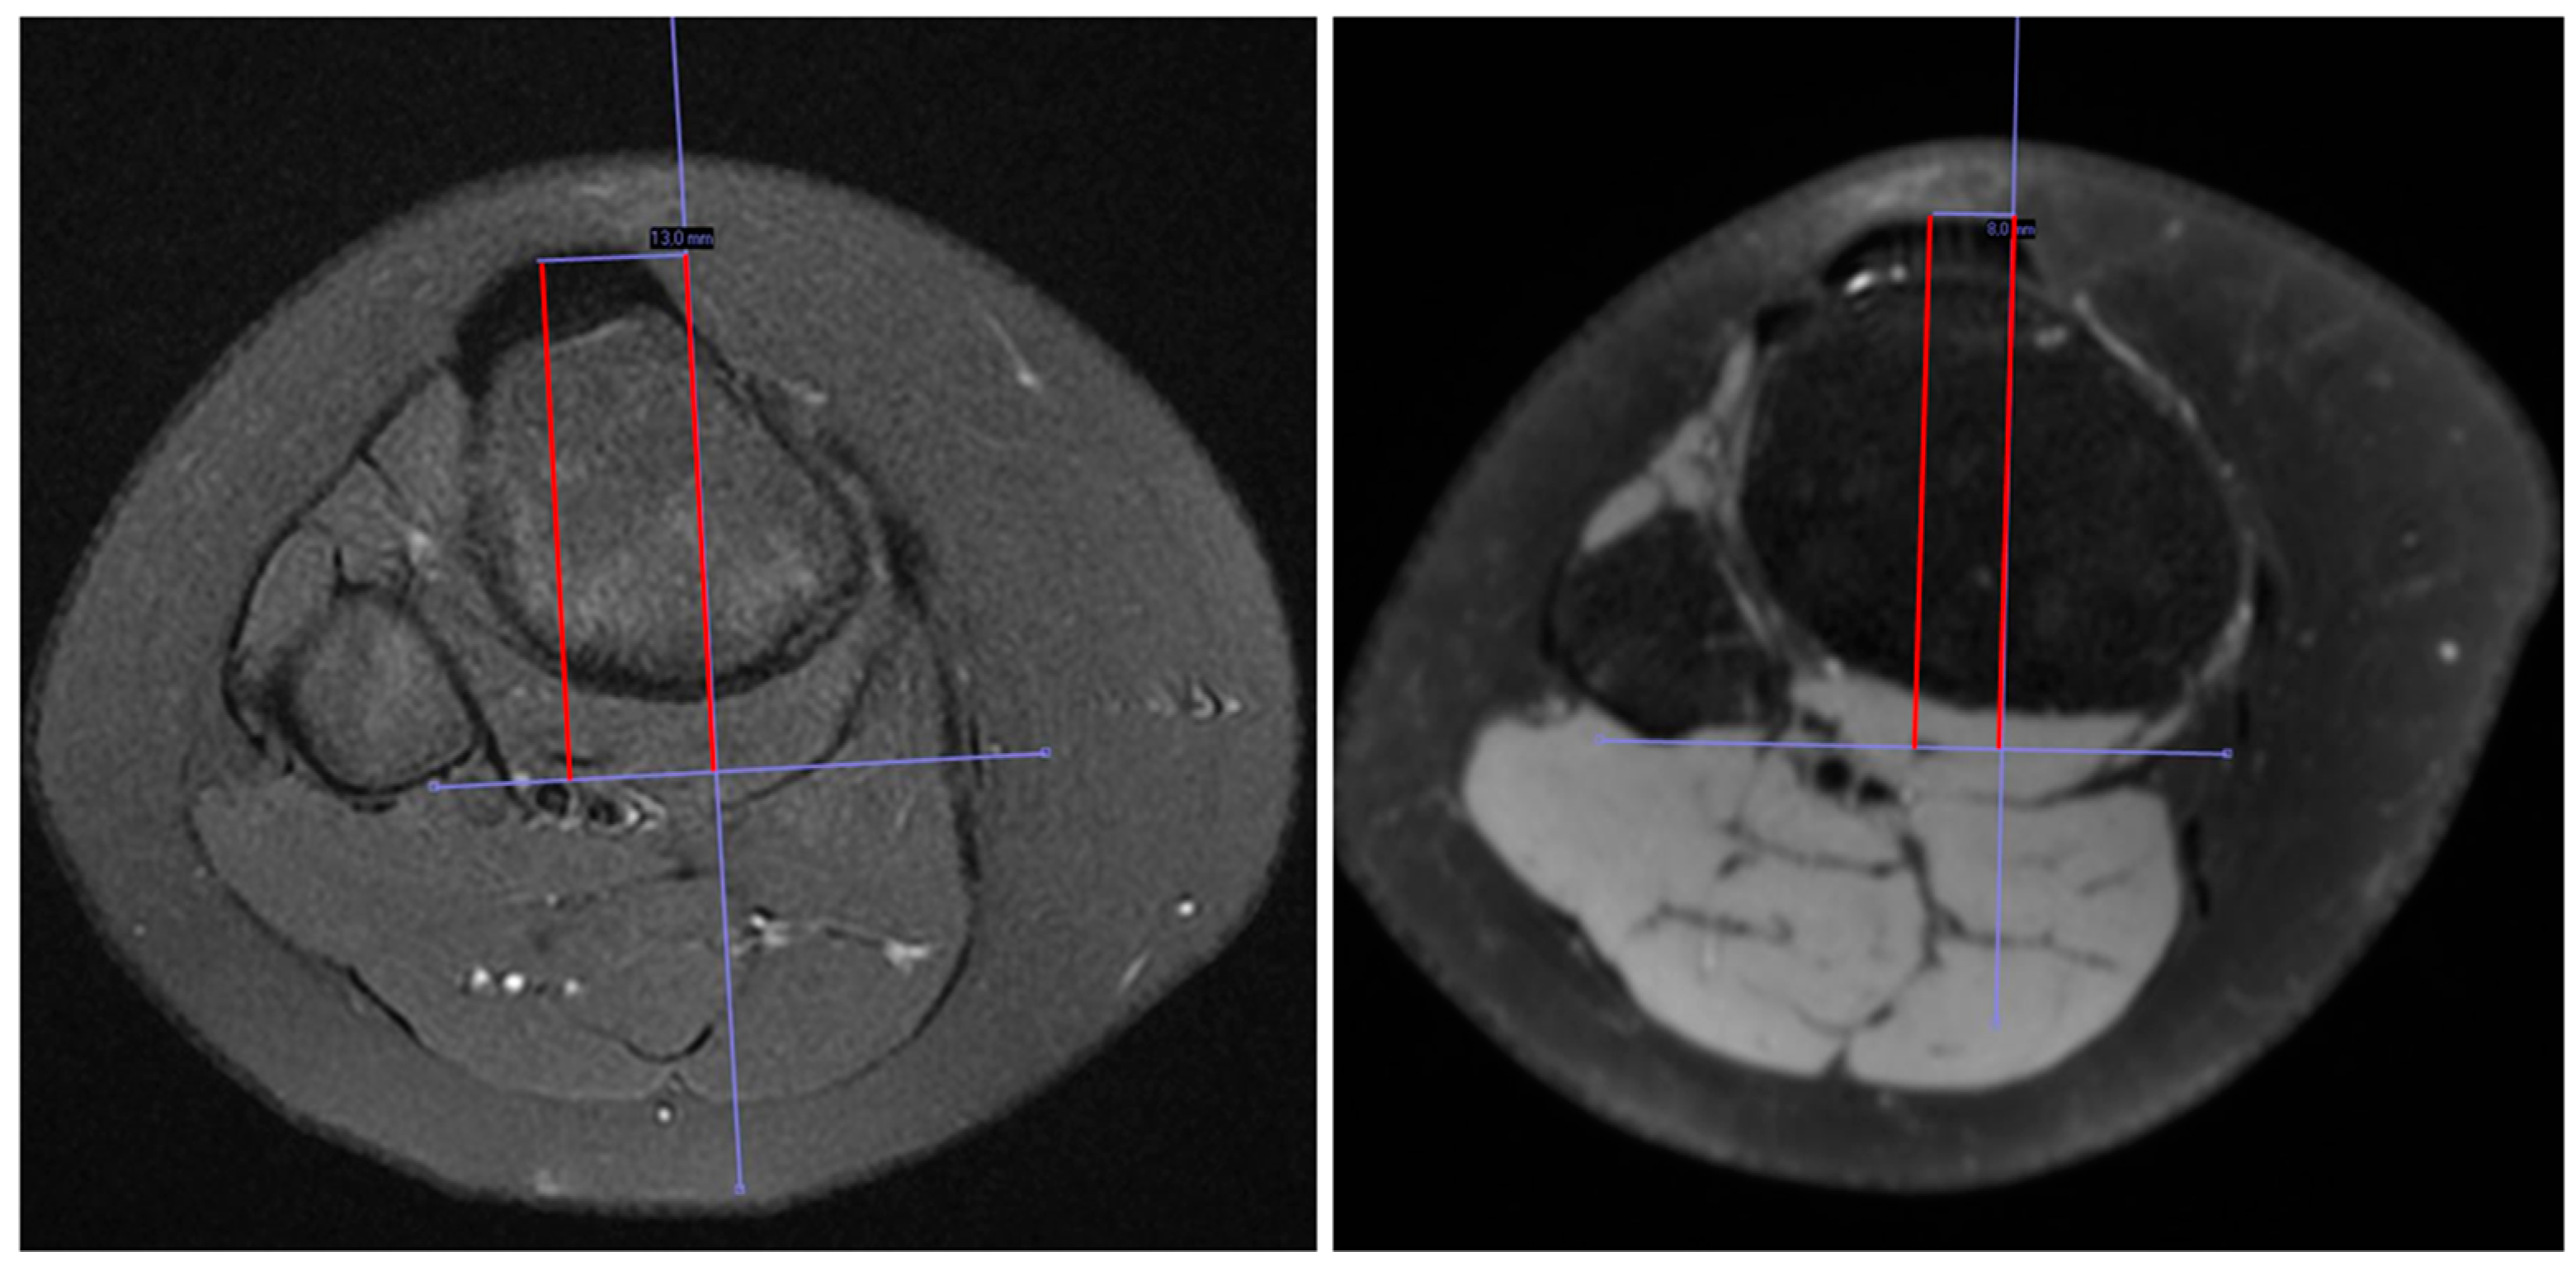

2.2. Radiological Measurement